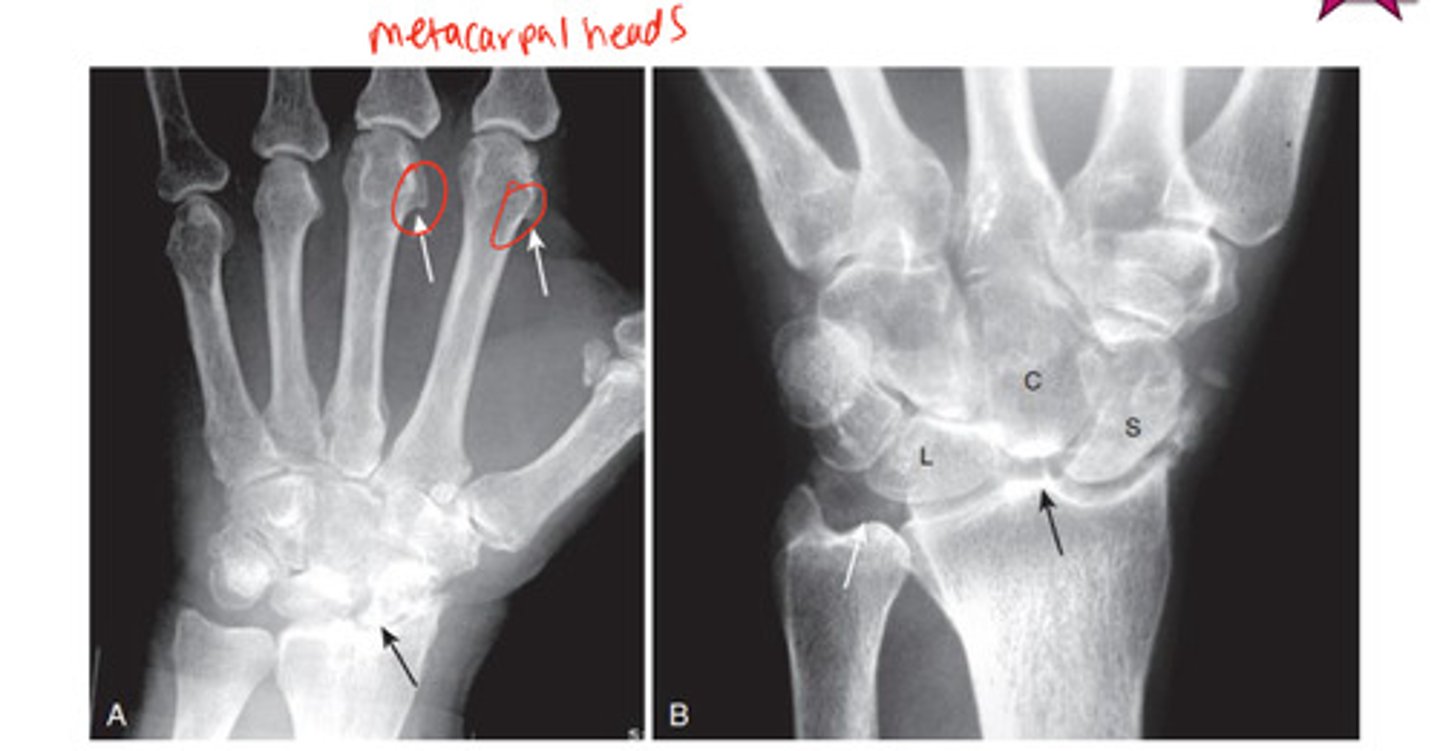

CPPD imaging

Ca2+ pyrophosphate disease- causing hook shaped deformity along 2nd & 3rd metacarpal head from osteophyte

RA

m/c in F; involves proximal joints of hands & wrists, usu B/L & symmetric

late findings of RA

ulnar deviation of fingers @ MCP, subluxation of MCP & ligament laxity leading to swan neck & boutonniere's deformities

gout

inflammatory changes incited by deposition of calcium urate crystals in the joint

M>F

monoarticular; asymmetrical later in course

what joint does gout m/c affect?

metatarsal phalangeal of the great toe

hallmark of gout

sharply marginated, juxtaarticular erosion that tends to have sclerotic borders ("rat bites")

gout imaging